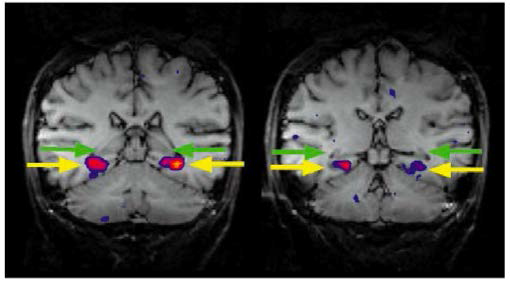

위 연구는 원본 사진과 섞여진(scrambled) 사진을 보고 사람이 인식할 수 있는지, 뇌가 어디가 어떻게 활성화되는지를 알아본 실험입니다. 여기서는 주요한 두 결과가 있습니다.

첫 번째는 우측으로 갈수록, 복잡한 사진일수록 사진을 이해하는 데 뇌를 많이 사용한다는 것입니다.

두 번째는 섞여진 사진의 경우 단순한 사진일수록 무엇인지 이해하기 더 쉽다는 것입니다. 사람의 얼굴이 섞여진 사진의 경우 눈, 코, 입 등을 파악하여 저것은 사람을 섞어놓은 것이구나를 알 수 있었으나 오른쪽으로 갈수록 어려움을 느꼈습니다.

즉 우리 뇌는 texture 같은 로우 레벨 picture에 많은 영향을 받는다는 것을 알았습니다. 이로 인해 사람들은 AI에도 Object Recognition에 많은 연구를 해야 한다고 생각했습니다.